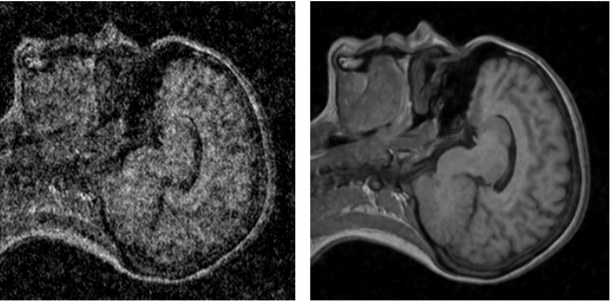

Помимо применения техники в фотографии, в частности в астрофотографии или съемке в темноте, разработчики также предложили применять ее для повышения качества снимков МРТ и продемонстрировали примеры работы алгоритма на таких снимках:

Фото: arxiv.org